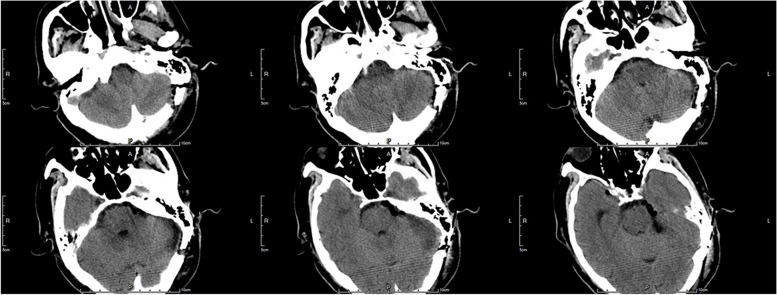

Case presentation: Two patients were presented with severe facial pain and preliminary diagnosis was TN. Preoperative magnetic resonance imaging revealed that a superior cerebellar artery (SCA) compressed the trigeminal nerve in case 1, and a tumor located in the petrous apex extending into the Meckel's cave compressed the trigeminal nerve in case 2. Operations were achieved through the EF-SCITA. The pain was totally relieved with no postsurgical complications in both cases.